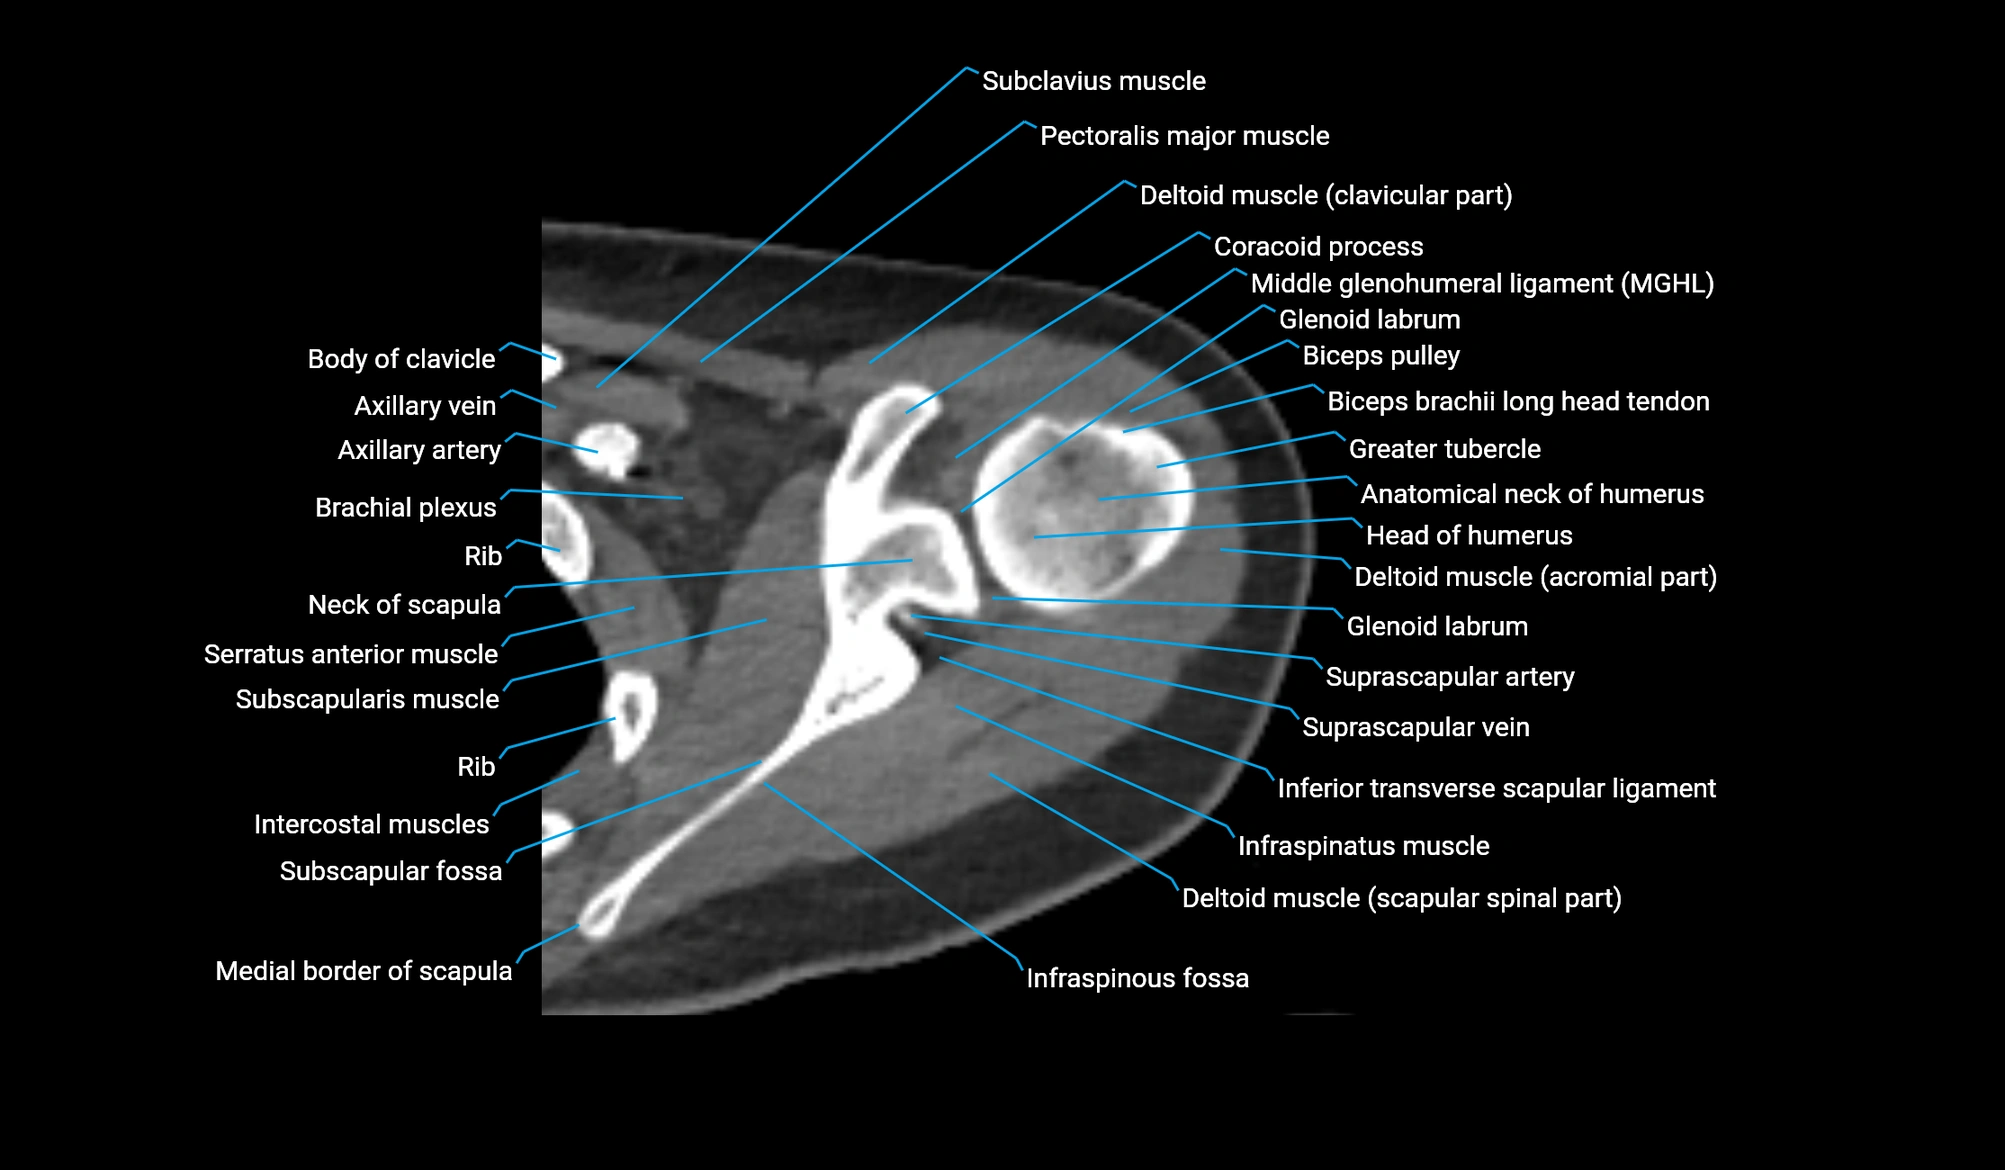

- Anatomical neck of humerus

- Biceps pulley

- Brachial plexus

- Coracoid process of scapula

- Glenoid labrum

- Head of humerus

- Inferior transverse scapular ligament

- Infraspinatus muscle

- Infraspinous fossa

- Middle glenohumeral ligament

- Neck of scapula

- Subclavius muscle

- Subscapular fossa

- Subscapularis muscle